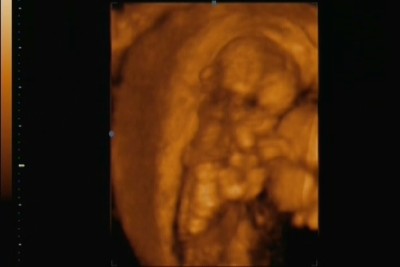

Ígértem tegnap képeket. :)

Hát ők lennének:

EgyiK:

Kép

Másik:

A dokira most is három órát vártunk... fél hatra voltunk berendelve... fél kilenckor sorra is kerültünk... (azzal bíztatott, hogy bár igyekszik a szüléshez beérni d elég nehéz így, hogy aránylag messze van egymástól a két kórház és az új munkahelye elsőbbséget élvez, de azért reménykedünk, hogy majd odaér... :( ) sajnos se képet nem tudot adni sem videóra felvenni, de elvittük a fényképezőgépet és azzal örökítettük meg az eseményeket...

Nagyon mókás volt mert elkezdtem nevetni amitől pocaklakónak földrengést okoztam... a látványtól meg nem bírtam abbahagyni a nevetést... kár, hogy a videót nemtudom feltenni...:lol: :lol: :lol: :lol: :lol: :lol: :lol: :lol: :lol:

A nemét még nem látni, de apja szerint tuiti lány mert egyfolytában járt a szája, meg dugdosta a nyelvét! :) :) :) :) :)